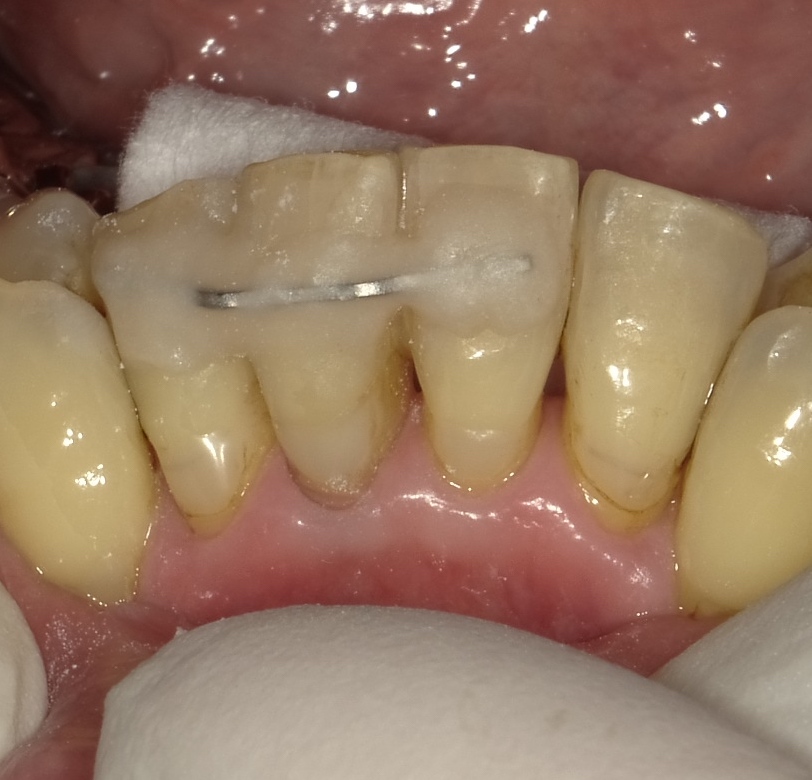

このような針金を用いて固定をします。

固定することで歯がグラグラせず食事も幾分楽に

なります。ただしこの固定は2、3週で外します。